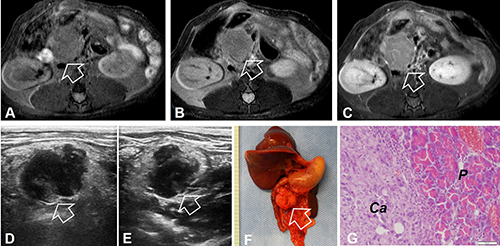

MR imaging showed irregular-shaped mass in the pancreatic head, demonstrated as homogeneous hypointensity on T1WI, hyperintensity on T2WI, and homogeneous enhancement 30 seconds after the intravenous administration of MR contrast agent, compared with the pre-enhancement T1WI (post- vs pre-enhancement signal intensity = 1261.9 ± 139.8 vs. 986.2 ± 114.9, P = 0.002) (Figure 2A–2C). For 6-week imaging follow-up of the animal group receiving bioluminescent active donor tumor tissues, the tumor grew from the average volume of 2.14 ± 0.21 cm3 to 4.13 ± 0.15 cm3, with an average growth rate of 0.49 ± 0.11 cm3 per week. On the ultrasound images, the tumors were shown as multilobulated inhomogeneous hypoechoic masses in the regions of pancreatic heads (Figure 2D and 2E). However, due to the deep-seated location of tumors in the abdominal cavity, which rendered the distance between the tumor and the skin beyond the penetration depth of bioluminescence, the majority of tumors were not visible in the bioluminescent optical images.

Figure 2: (A–C) MR images of the orthotopic pancreatic head cancer of a recipient rat. The tumor appears as homogeneous hypointense signal on axial T1WI (arrow on A), homogeneous hyperintense signal on T2WI (arrow on B), and heterogeneous enhancement on contrast-enhanced T1WI (arrow on C). (D and E) Ultrasound imaging demonstrates the tumor mass as inhomogeneously hypoechoic intensity on the transvers and longitudinal images (arrows). (F) Photograph of the gross specimen shows a typical pancreatic head tumor (arrow). (G) Histology with H&E staining confirms the formation of the pancreatic ductal carcinoma (Ca) and the normal pancreas (P).

Pathologically, 7 (26%) of 27 animals with tumors developed disseminated metastatic foci in the retroperitoneum, greater omentum, mesentery, and intestines at the end of the 6-week follow up post-tumor implantation. Three (15%) of 27 rats developed bloody and malignant ascites with obvious sign of cachexia. Microscopically, the tumors displayed as a moderately to well differentiated ductal pancreatic carcinomas (Figure 2F and 2G).